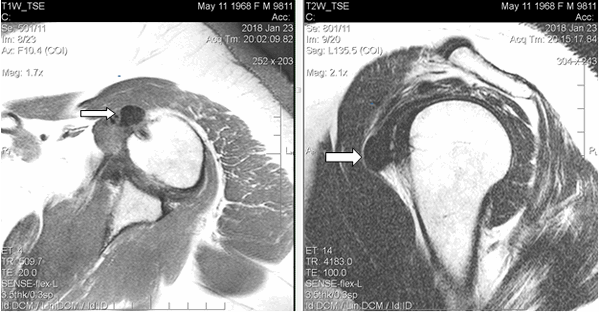

Материал и методы исследования. Проанализированы клинико-лучевые данные пациентки Л., 49 лет, впервые обратившейся в медицинский диагностический центр МРТ и КТ ООО «Нью МРТ и КТ на Зубковой» г. Рязани в январе 2018 года по направлению врача-ортопеда. Пациентка предъявляла жалобы на боль в левом плечевом суставе (дельтовидной области), лечилась консервативно (нестероидные противовоспалительные средства, блокады) с временным положительным эффектом. Из анамнеза известно, что около двух лет назад при дорожно-транспортном происшествии пациентка получила травматический перелом правой ключицы с последующим довольно длительным заживлением, но повреждений левого плечевого сустава выявлено не было. Данный факт позволяет высказаться о вынужденной длительной повышенной функциональной нагрузке на здоровую (левую) верхнюю конечность (пациентка правша).

МРТ выполнено на высокопольном аппарате Philips Intera (индукция магнитного поля 1,5 Тл) с использованием гибкой катушки для плечевого сустава. Протокол магнитно-резонансной томографии включал следующие последовательности: Т1-ВИ аксиальные, Т2+pd+fs ВИ аксиальные, Т2-ВИ корональные, Т2+pd+fs ВИ корональные, Т2-ВИ или PD+fs сагиттальные срезы с толщиной по 3,5 мм. Общее время сканирования составило около 20 минут. Компьютерная томография (КТ) выполнена на 40-срезовом компьютерном томографе Philips Brilliance.

Результаты исследования и их обсуждение. При магнитно-резонансной томографии, (январь 2018 г.) в левом плечевом суставе выявлены умеренные дегенеративные изменения в виде краевых заострений суставной впадины лопатки, кальцинат в субдельтовидной сумке размерами 1,5х1,2 см, субхондральная киста акромиона диаметром до 0,4 см, небольшое количество выпота в субдельтовидно-субакромиальной сумке. Таким образом, МР-картина соответствовала акромиально-ключичному артрозу II стадии, плечелопаточному артрозу I стадии; выявлены субдельтовидно-субакромиальный бурсит, оссифицирующий капсулит плечевого сустава (рис. 1). Рекомендована консультация ортопеда.

![]()

Рис. 1. МРТ левого плечевого сустава пациентки Л., 49 лет (январь 2018 г.), Т1-ВИ, аксиальный срез (а) и Т2-ВИ, сагиттальный срез (б). В субдельтовидном пространстве в зоне отрога капсулы сустава вдоль сухожилия длинной головки на 9 часах условного циферблата головки плечевой кости визуализируется крупный кальцинат (обозначен стрелками) в виде гомогенно-гипоинтенсивного на Т1-ВИ и Т2-ВИ образования неправильно-округлой формы с четкими контурами размерами 1,5х1,2х1,1 см, без перифокального отека, деформирующий передний пучок дельтовидной мышцы